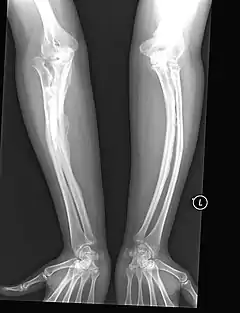

- يولدون بكسور متعددة وتبين الأشعة السينية التأم بعض الكسور أثناء مراحل نمو الجنين داخل رحم الأم.

عند التشخيص يتم ملاحظة الأعراض المرافقة ويتم أخذ عينة من الجلد لإجراء الفحوصات على الكولاجين، أيضاً تؤخذ عينة دم لإجراء الفحوصات والتحاليل على دي ان اي ( DNA). يتم تشخيص العظام في معظم الحالات عن طريق الأشعة السينية.